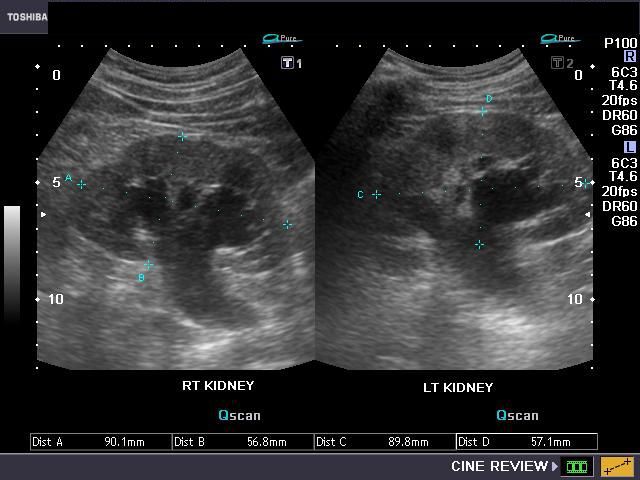

Urinary bladder wall trabeculation in a case of Lower urinary tract obstruction

Sonography of the urinary system was done on this elderly male patient having lower urinary tract symptoms. Ultrasound images show evidence of trabeculation of the urinary bladder. This is seen as folds of hypertrophied bladder mucosa and bladder smooth muscle. There is also evidence of bilateral moderate hydronephrosis (image top right). The cause of Lower urinary tract obstruction appears to the enlarged prostate (benign prostatic hypertrophy) with intravesical enlargement of the median lobe (image on lower left). The fourth image shows significant post-voiding residual urine in the urinary bladder (Ultrasound image on lower right).

All images by Joe Antony, MD, using a Toshiba Nemio-XG ultrasound system.